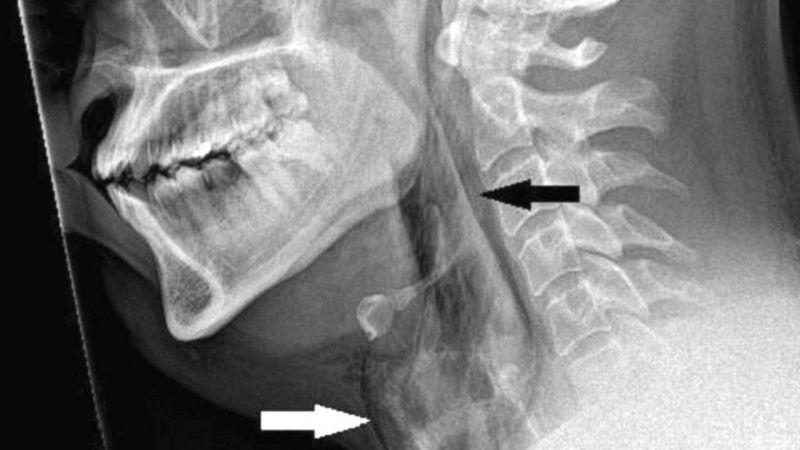

Un equipo médico emitió una advertencia después de que un hombre se perforara la garganta cuando intentó detener un estornudo.

El paciente, de unos 30 años, fue trasladado al hospital Ninewells, en Dundee, Inglaterra, con fuertes dolores, después de haberse apretado la nariz y cerrado la boca para reprimir el estornudo.

Las exploraciones revelaron que sufrió un desgarro de 2 mm en la tráquea.

Los médicos de la Universidad de Dundee dijeron que si se cierra la boca y la nariz durante un estornudo, la presión en las vías respiratorias superiores puede aumentar unas 20 veces.

Cuando los médicos examinaron al paciente, escucharon un crujido al tocarle el cuello y descubrieron que no tenía control de movimiento.

Un desgarro repentino de garganta, conocido médicamente como "ruptura traqueal espontánea", es poco común y puede ser potencialmente letal.